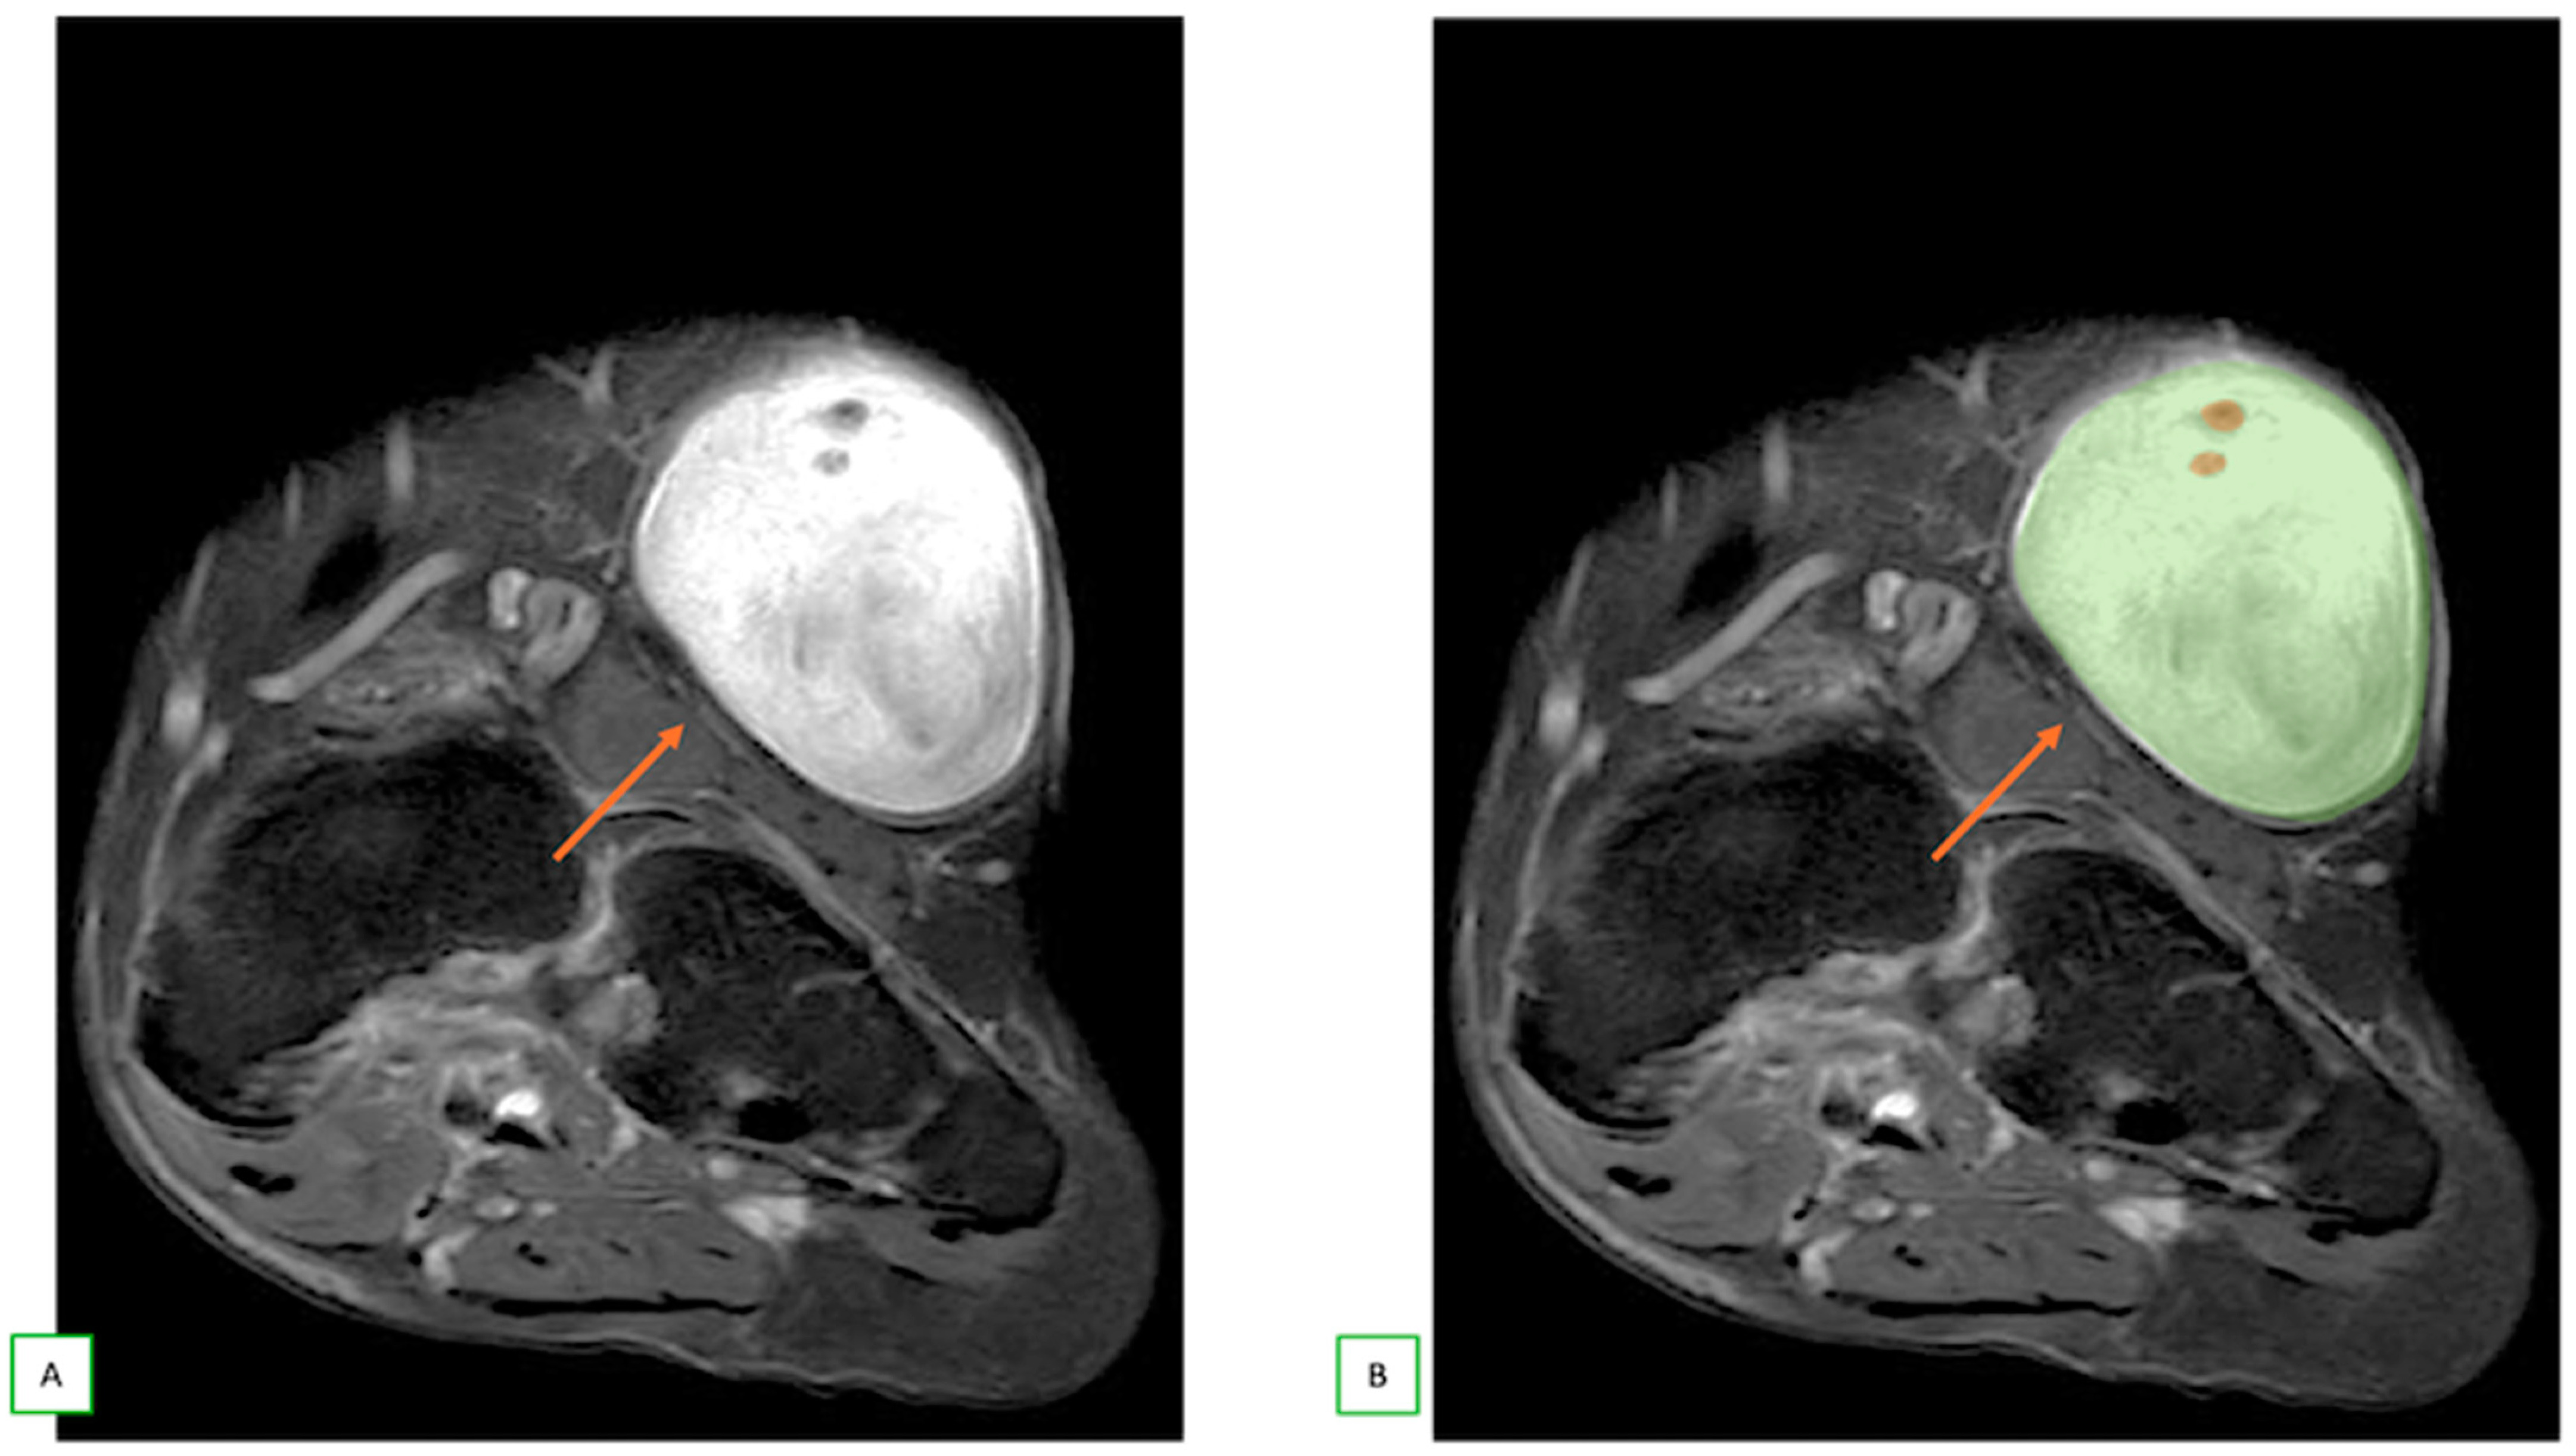

- Primary Sarcomas: Soft-tissue sarcomas are uncommon, accounting for just over 1% of adult malignancies. Synovial sarcoma, clear cell sarcoma, and epithelioid sarcomas are known to involve peripheral nerves. CT/MR reveals a large soft tissue mass with areas of necrosis or calcification and heterogeneous contrast enhancement. F-18 FDG uptake is useful for both tumor staging and treatment assessment (Figure 26, Figure 27 and Figure 28).